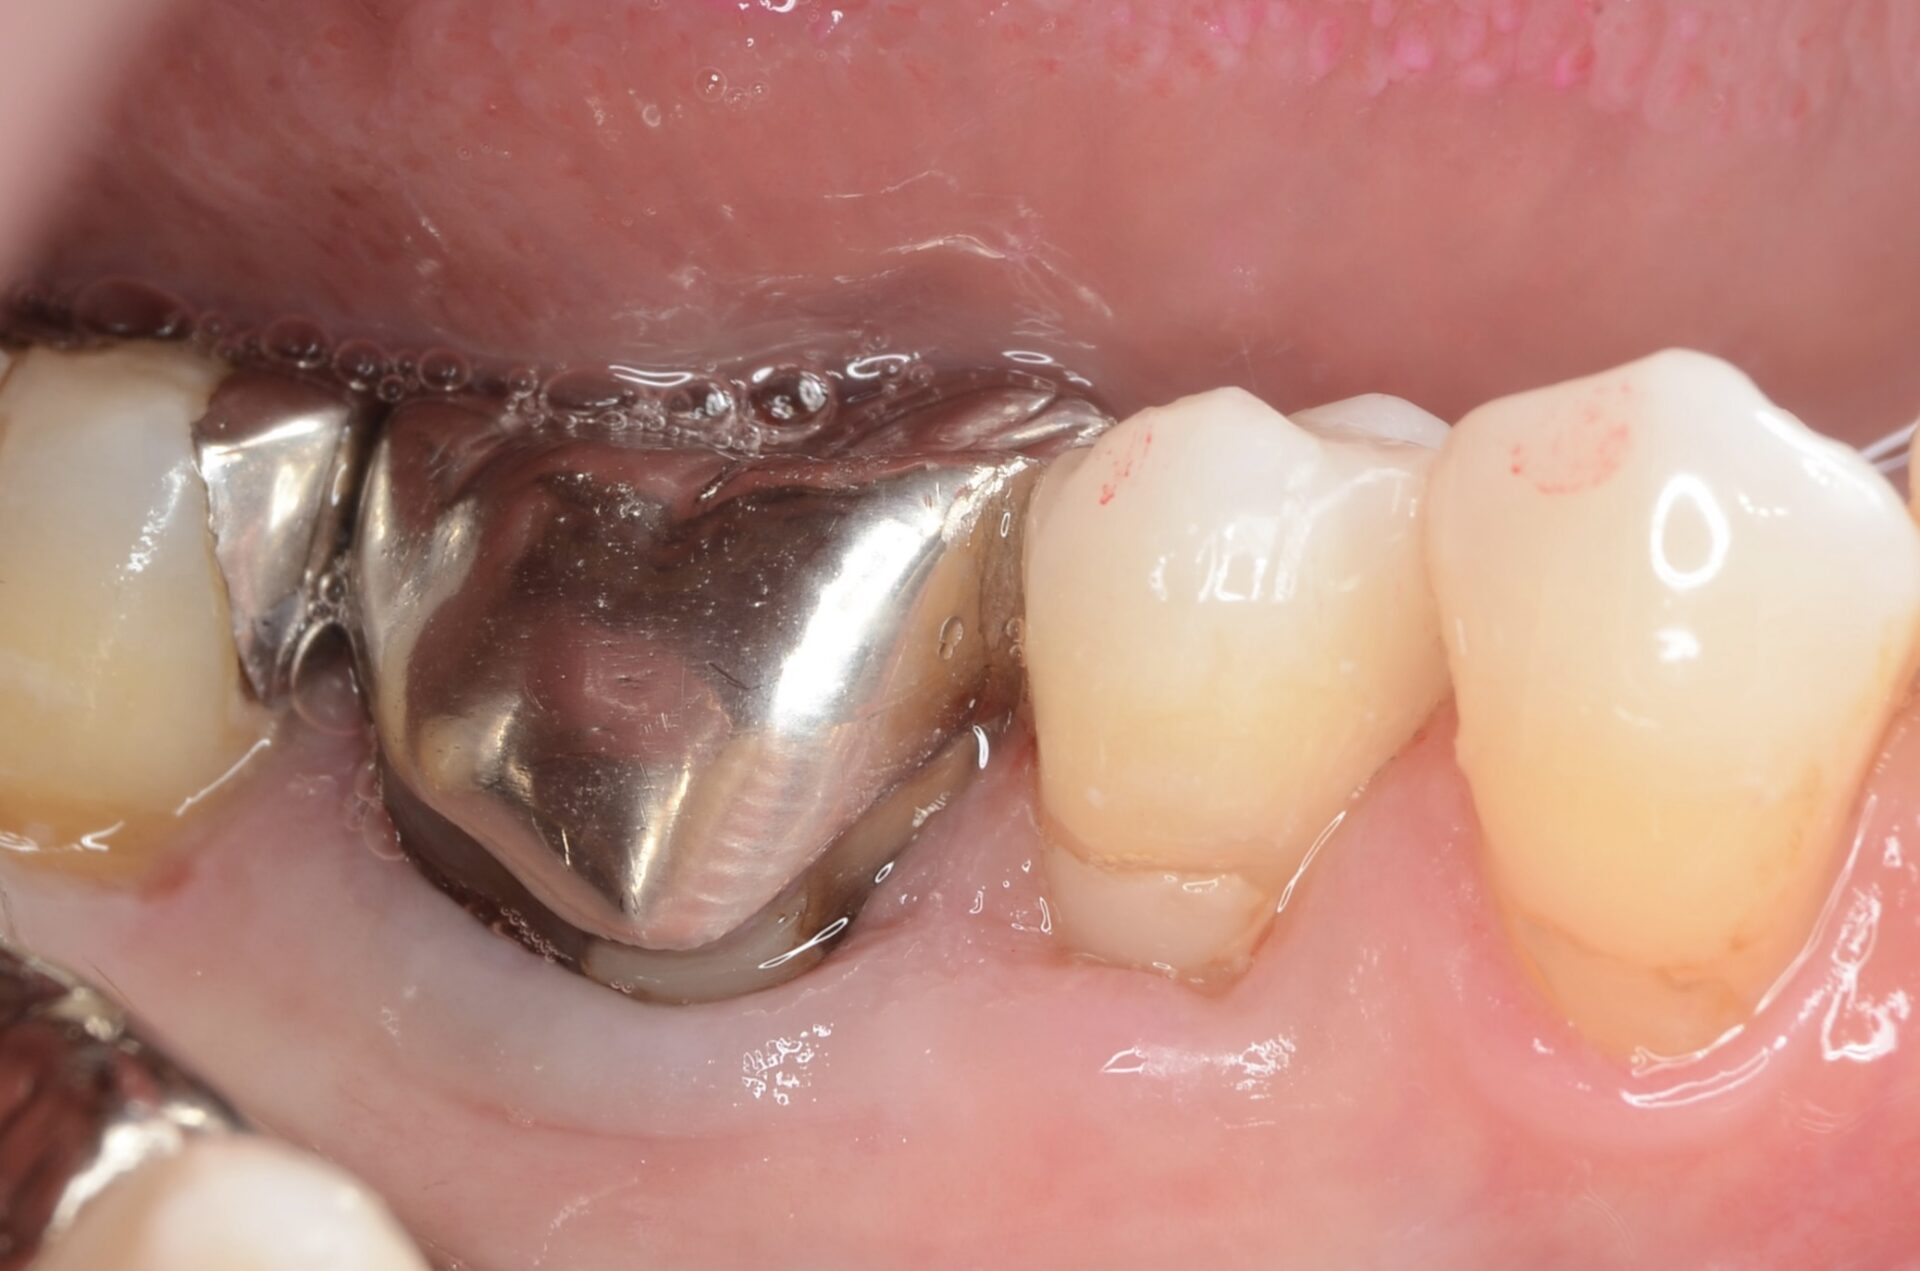

保険治療のクラウンで

-

クラウン除去